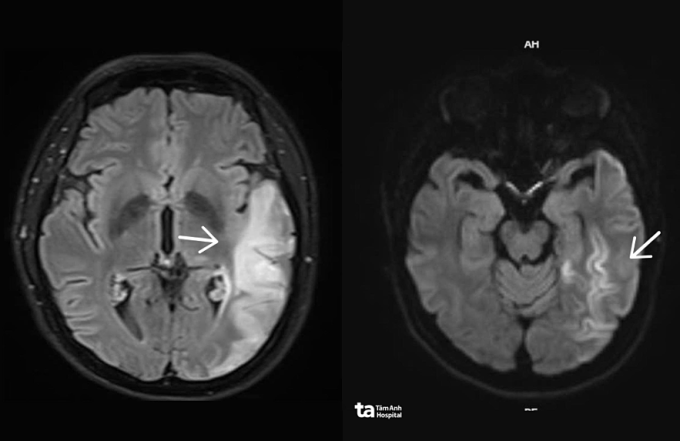

BS.CKI Đặng Khắc Giáp, Trung tâm Khoa học Thần kinh, Bệnh viện Đa khoa Tâm Anh TP HCM, cho biết hình ảnh MRI 3 Tesla của chị Thu có tổn thương não lan rộng bất thường song không phù hợp với các đặc điểm điển hình của đột quỵ do tắc mạch hay viêm não. Người bệnh thể trạng nhỏ, gầy, đái tháo đường khởi phát từ khi còn trẻ - dấu hiệu rối loạn chuyển hóa năng lượng. Kết quả xét nghiệm chuyển hóa chuyên sâu cho thấy bất thường rõ rệt trong quá trình oxy hóa năng lượng tại não, nghi ngờ bệnh lý ty thể.

Hiện, y học chưa có phương pháp điều trị khỏi hoàn toàn bệnh ty thể. Người bệnh chủ yếu được điều trị kiểm soát bệnh, dự phòng biến chứng. Bệnh được chẩn đoán sớm và theo dõi thông qua kết hợp lâm sàng, chụp MRI 3 Tesla, MRI phổ, xét nghiệm chuyển hóa, phân tích gene.